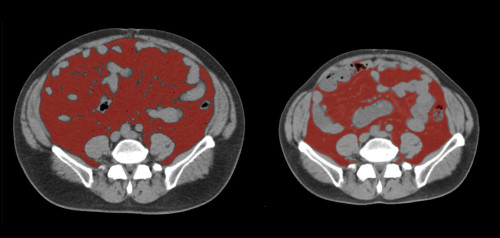

①

50代・女性(ご本人のご厚意で画像提供)

治療内容:チルゼパチド7.5mgの週1回自己注射による脂肪減少と脂肪肝改善

治療期間: 12ヶ月(52週)((用量は2.5mgから開始し最大で15mg。減量効果が得られる必要用量には個人差があります。))

費用:自由診療の場合は9900円(税込)×52(週)=514800円

想定されるリスク・副作用:下記に副作用を記載

※医療広告ガイドラインに準拠して表記

1:脂肪の減少

皮下脂肪の減少(赤色部分)